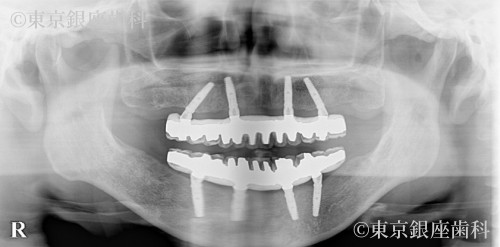

数年以上にわたり、歯科医院に通院できなかったため、全顎的に歯周病が重度に進行してしまった。その結果、何本もの歯が自然に抜け落ちてしまい、また差し歯も外れてしまった。奥歯で安定して咬むことができず、咬み合わせることができる場所が前歯しかなかったので、長期にわたり前歯を中心に咀嚼を続けていた。その結果、前歯に対する過剰な負担がかかってしまい、前歯を支える周りの骨の著しい吸収と、前歯の位置の変化が認められた。また奥歯の支えがなく、顔の周囲の筋肉が十分な機能を果たしていなかったため、表情筋の張りが不足していることが認められた。

患者様の主訴である見た目の改善をするために、奥歯での咬み合わせを安定させることで、口腔機能の回復させ、同時に審美の改善もはかる計画を立てました。上下顎ともに残っている歯のほとんどが重度の歯周病と過剰な咬み合わせの力により、歯の周りの骨の吸収が著しかったため、全顎的な抜歯と、ワンデイインプラント治療による口腔機能・審美の改善をはかることを計画いたしました。また歯科治療に対する極度の恐怖症だったため、静脈内鎮静を併用することを予定しました。